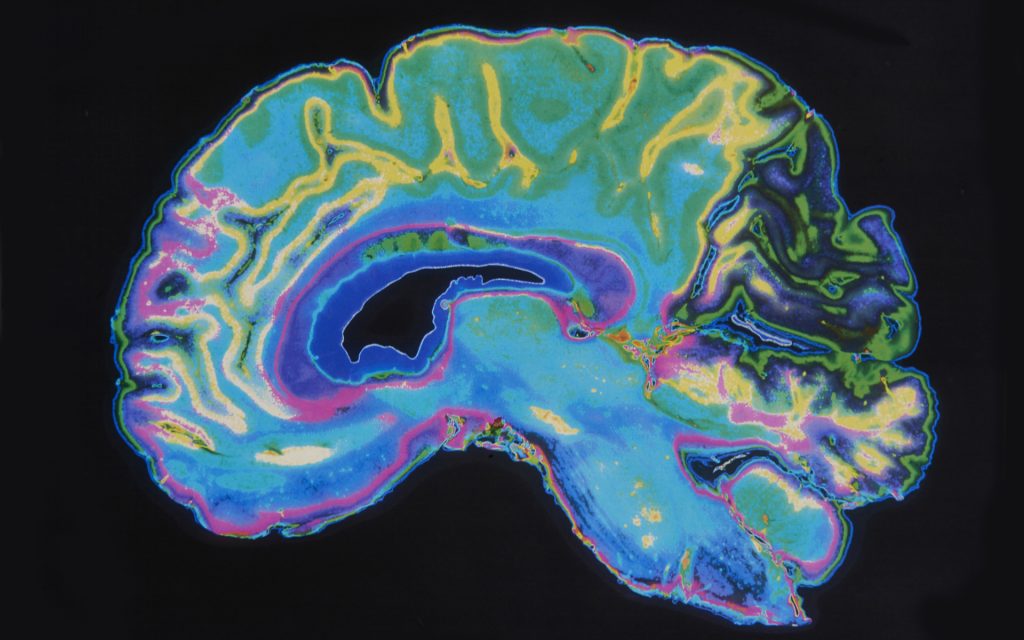

Scientists from Weill Cornell Medicine reviewed recordings from fMRI scans that suggest these substances essentially flatten the landscape of your brain, making it easier to jump between tasks.

In the study, researchers tracked the effects of LSD and psilocybin on brain activity using functional magnetic resonance imaging (fMRI) recordings of the brain activity of volunteers. Each volunteer underwent two scanning sessions. One session included a dose of LSD or psilocybin, the other a placebo.

Their new approach, which they dubbed network control theory, uses a clustering algorithm to categorize a data set that represents a network’s activities as distinct patterns, or states. In the study, the meta-view of the network’s state-to-state transitions illustrated that psychedelics lowered, or ‘flattened,’ the minimum energy barriers required to transition between states, “allowing the brain to transition from one state to another much more readily,” according to the results.